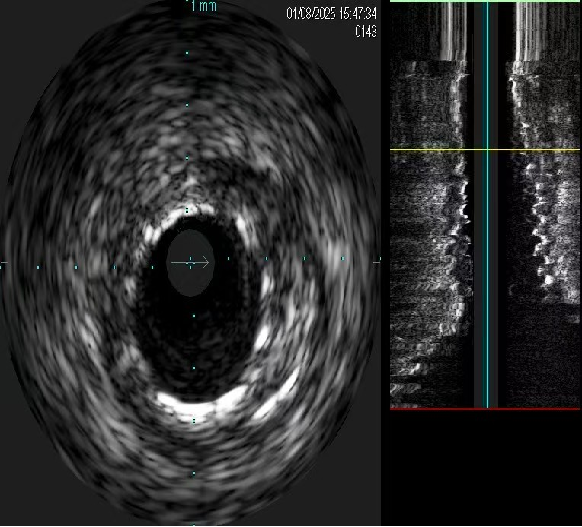

先后送入Stent 1(2.5x33mm Firebird2)、Stent 2(3.0x18mm Firebird2)、Stent 3(3.5x33mm Firebird2)、Stent 4(4.0x23mm Firekingfisher)由RCA远端至开口串联。

进入Ballon 7(3.0X12mm NC Sprinter)至Stent 1-2内由远及近以8-18atm后扩张,送入Ballon 8(4.0x12mm Grip)至Stent 3、4以12-20atm后扩。

送入IVUS导管查看支架开放良好、贴壁良好,未见夹层、血栓等 并发症。